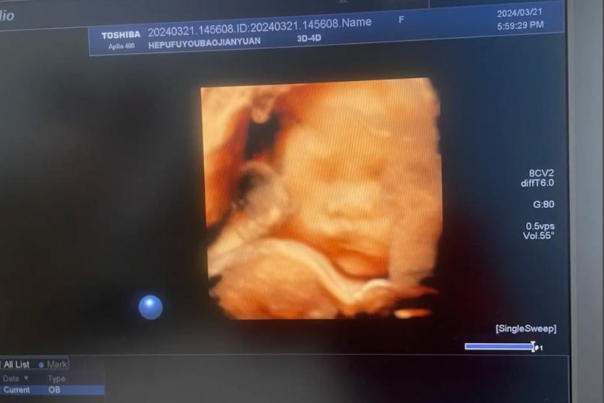

随着医疗技术的进步,四维彩色超声检查已成为孕期检查的重要环节,它不仅能为准父母提供胎儿动态影像,更成为民间猜测胎儿性别的新途径。近期,"看四维胎儿面孔看男女"的话题在社交媒体上引发热议,部分网友通过观察胎儿面部特征判断性别,甚至形成"尖下巴是女儿,圆脸是儿子"等经验性结论。然而,这种猜测是否具有科学依据?四维彩照的真实意义又是什么?本文将结合医学原理与社会现象,为您揭开真相。

四维彩照作为孕期检查的"黄金标准",其核心价值在于通过动态影像观察胎儿发育情况,而非性别鉴定。根据《产前诊断技术管理办法》规定,非医学需要的胎儿性别鉴定属于违法行为,医疗机构不得实施。事实上,胎儿的面部特征、肢体动作主要受遗传因素、发育阶段及个体差异影响,与性别无直接关联。

四维彩超的核心设计初衷,是用于医学筛查,其主要任务是评估胎儿的重大结构畸形,如唇腭裂、脊柱裂、心脏及四肢发育异常等。它的优势在于呈现表面形态和动态过程,但其图像清晰度受多种因素影响,如孕周、羊水量、胎儿体位、孕妇腹壁厚度等。在诸多条件限制下,胎儿的面部细节(如下巴的方圆、鼻梁的高低)往往显得较为模糊,且带有一定的主观成像伪差,据此进行精细的性别判断,其准确性根本无法保证。